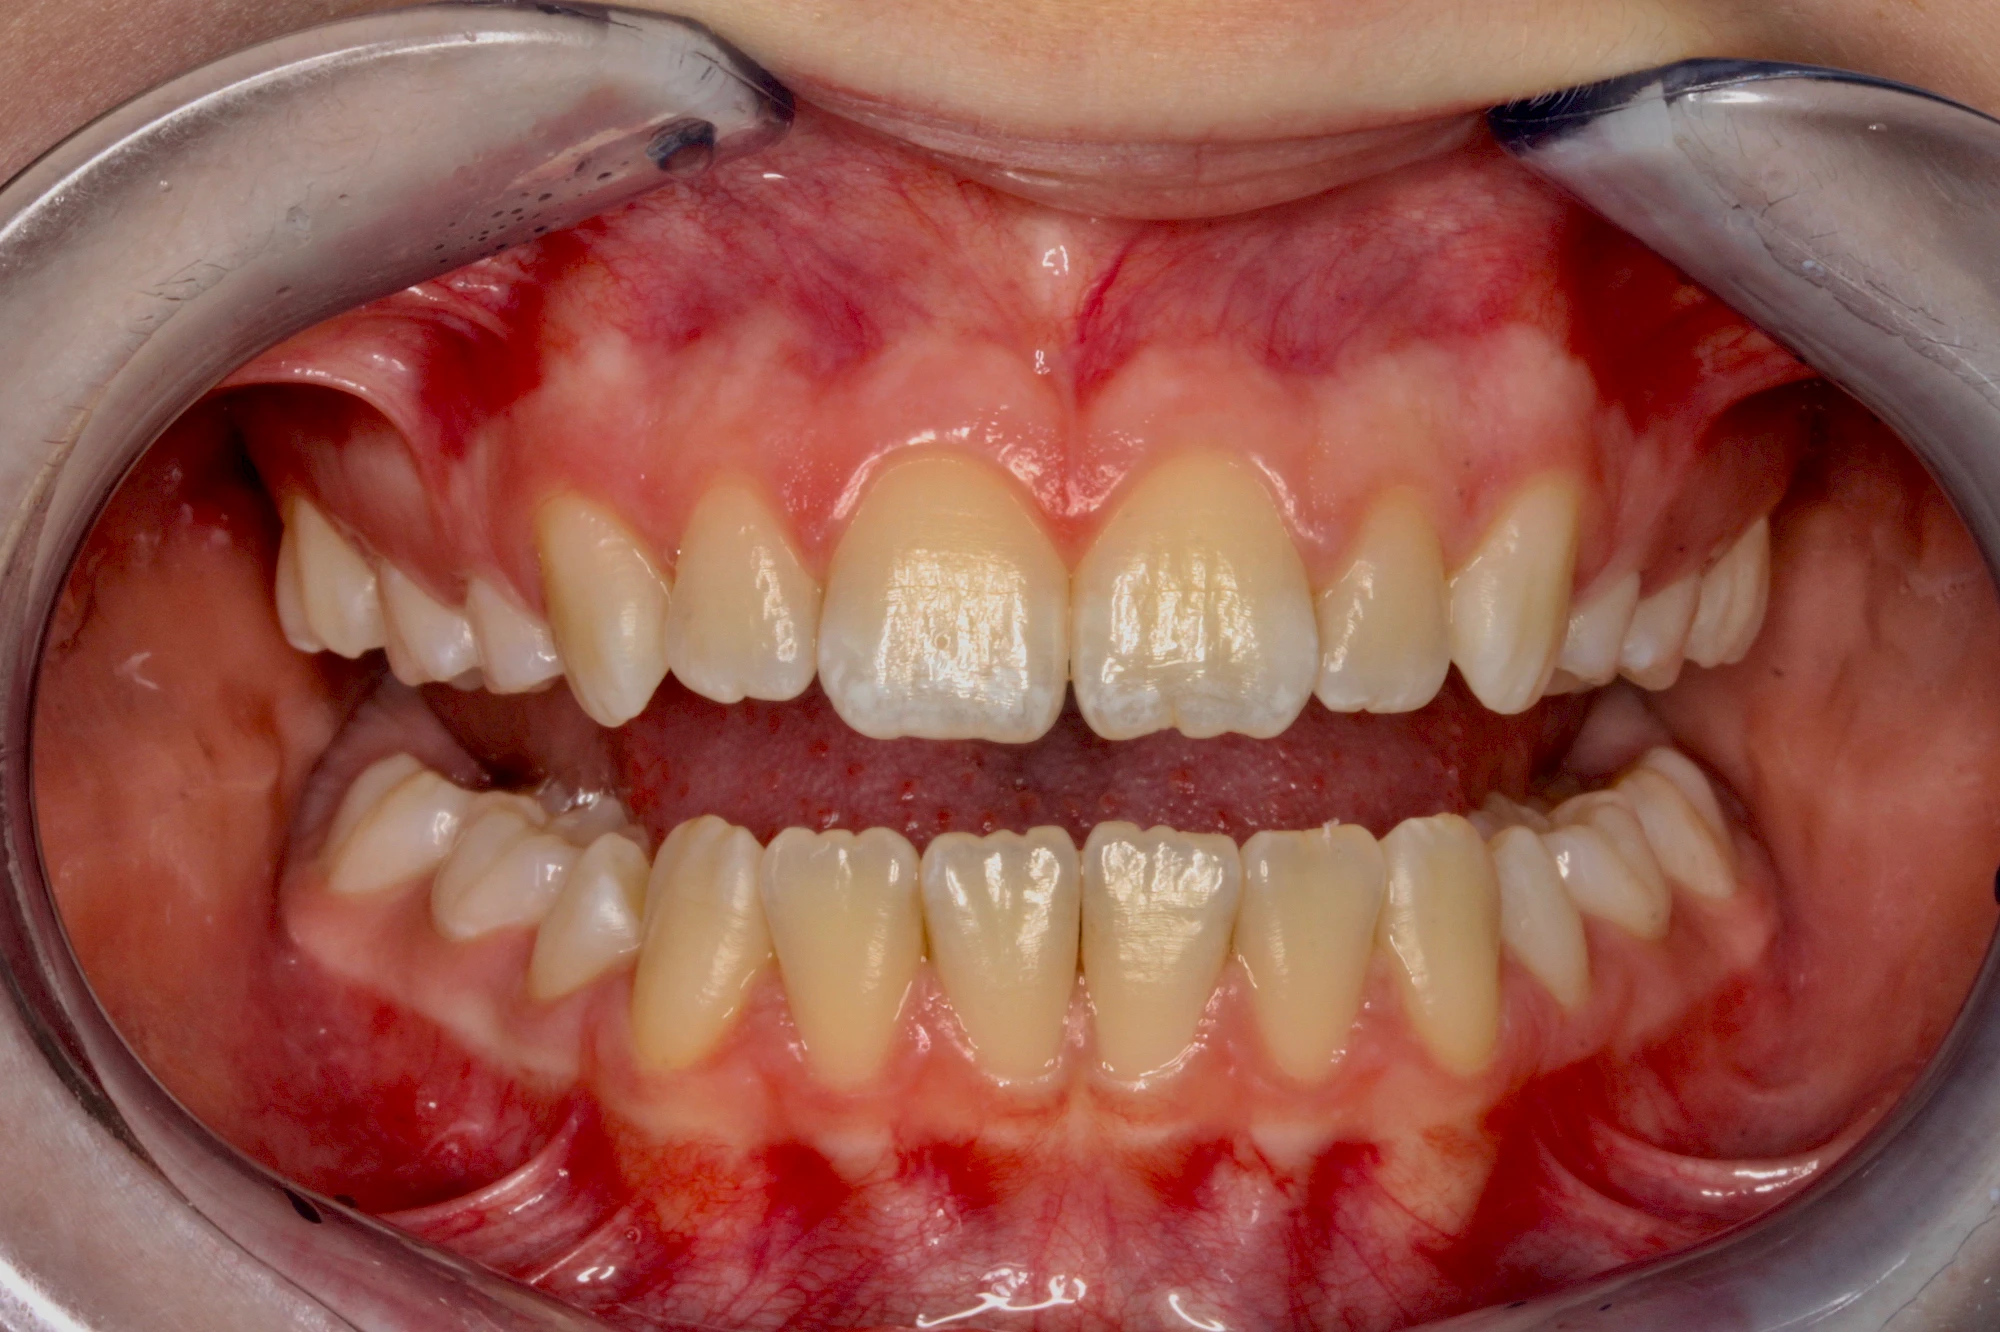

Verfärbungen an Zähnen können außen aufgelagert oder im Zahn eingelagert sein.

Von außen (exogen) eher dunkel gefärbt und meist mehrere Zähne betroffen:

- Durch übermäßige Fluorideinlagerung in der Zahnreifung (mehrere Zähne, weißlich-fleckig)